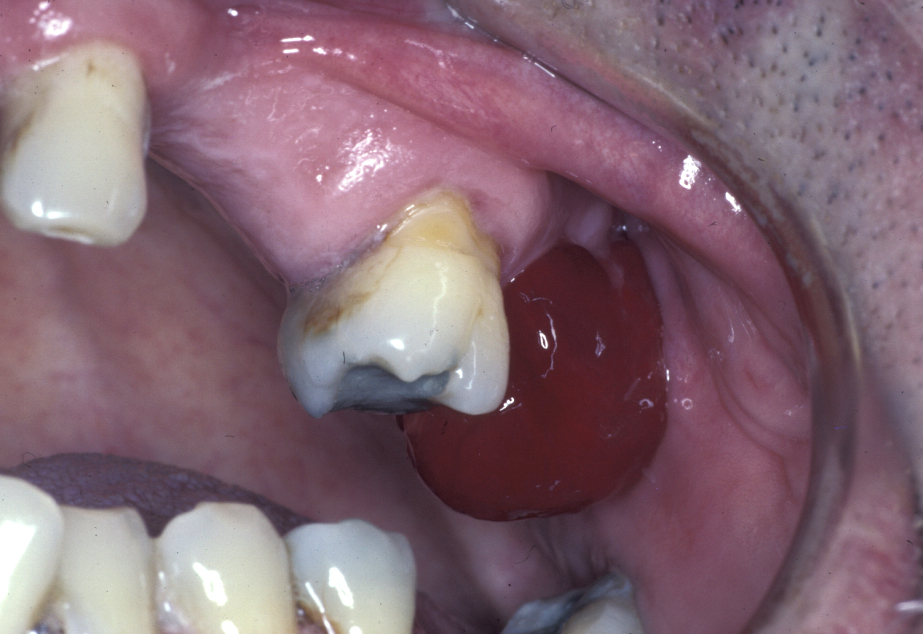

An established (chronic) oroantral fistula (Figure 3) leads to bouts of recurrent maxillary sinusitis, there may be a foul taste in the mouth, and fluids may be passing from the mouth through the fistula and out of the nose. The fistula can be demonstrated by occluding the nose and blowing out through the nose: air will be seen to bubble out of the fistula. A plain X-ray radiograph helps to identify any fragments of retained roots in the sinus.

Figure 3: Chronic oroantral fistula. Very rarely this can be a sign of an underlying malignancy.